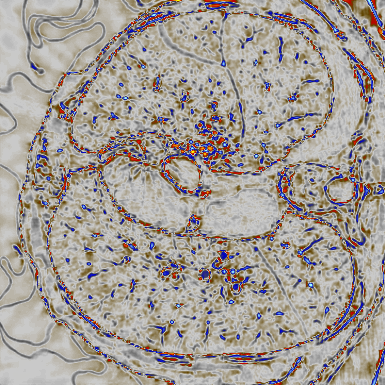

Deep learning-based image reconstruction approaches have demonstrated impressive empirical performance in many imaging modalities. These approaches generally require a large amount of high-quality training data, which is often not available. To circumvent this issue, we develop a novel unsupervised knowledge-transfer paradigm for learned iterative reconstruction within a Bayesian framework. The proposed approach learns an iterative reconstruction network in two phases. The first phase trains a reconstruction network with a set of ordered pairs comprising of ground truth images and measurement data. The second phase fine-tunes the pretrained network to the measurement data without supervision. Furthermore, the framework delivers uncertainty information over the reconstructed image. We present extensive experimental results on low-dose and sparse-view computed tomography, showing that the proposed framework significantly improves reconstruction quality not only visually, but also quantitatively in terms of PSNR and SSIM, and is competitive with several state-of-the-art supervised and unsupervised reconstruction techniques.